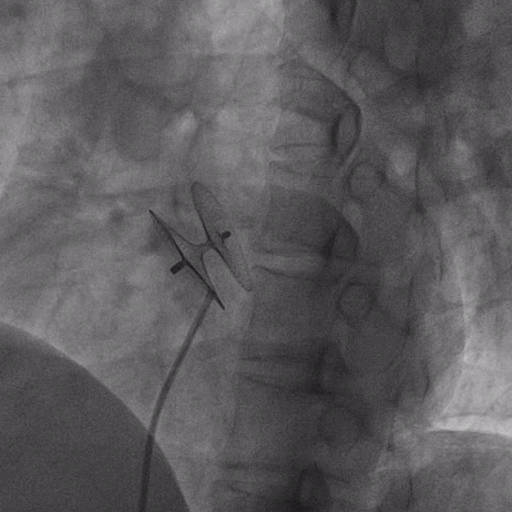

在獲得患者同意后,1月12日,尚福軍主任為患者進行了PFO封堵術(shù)。術(shù)中造影可見封堵器殘余漏,尚福軍主任用精湛的技藝,順利通過封堵器殘余漏裂縫,將右心導管從右房送入左房,且順利到達肺靜脈;遂行卵圓孔未閉封堵術(shù)后殘余漏再次封堵;且完美釋放PFO封堵器,可見兩封堵器呈“馬蹄蓮”狀,再次術(shù)中造影未見殘余漏。